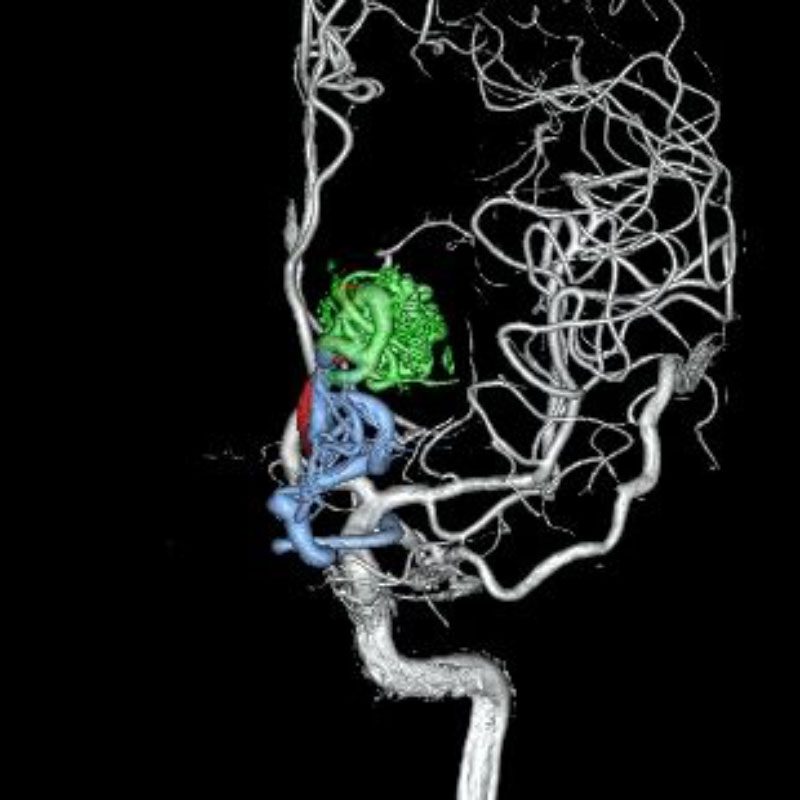

脳動静脈奇形

血管塞栓術

松田/濵田/元永